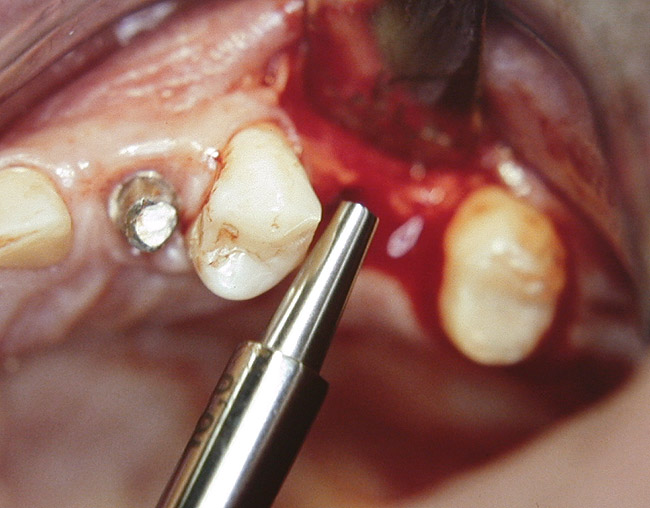

At the time of surgery, local infiltrative anesthesia was administered (lidocaine 2% with epinephrine, 1:100,000). A full-thickness mucoperiosteal flap was raised. The initial osteotomy was performed on midcrestal bone using a rose-headed bur. To prepare the osteotomy site for implant placement, sequential alternating osteotomes with variable conicity were used, drilling 2-mm shorter than the length of the implant to be placed (Figure 3A and Figure 3B). The implants presented initial primary stability (Figure 4), the cover screws were placed, and the implants were submerged for a healing period. The tissue was approximated, and the patient was instructed not to wear any denture or to place pressure on the healing site.

Figure 3a  Alternating osteotomes with variable conicity used to perform the alveolar remodeling in the area of tooth No. 24.

Figure 3a

Figure 3b  Alternating osteotomes with variable conicity used to perform the alveolar remodeling in the area of tooth No. 24.

Figure 3b